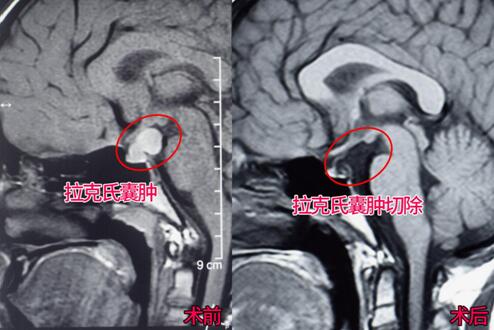

入院后,周忠清主任仔细阅读小尼的影像资料发现:小尼的颅内病变是以垂体柄为后方的囊性病变(1×2.5cm),无钙化,病变性质首先考虑拉克氏囊肿,并不符合典型的颅咽管瘤影像特征。

2月22日,小尼被推进了手术室。经过近3小时的手术,囊壁得到了充分切除,取出的囊内容物为灰色半固态-半胶冻样,没有看见钙化,垂体柄和垂体也得到了完好的保护。术后,小尼恢复的很快,各项功能正常,过了两三天就可以下地走路,还总爱和妈妈吵着要手机玩。术后经过病理检查,病变性质为确认为拉克氏囊肿。